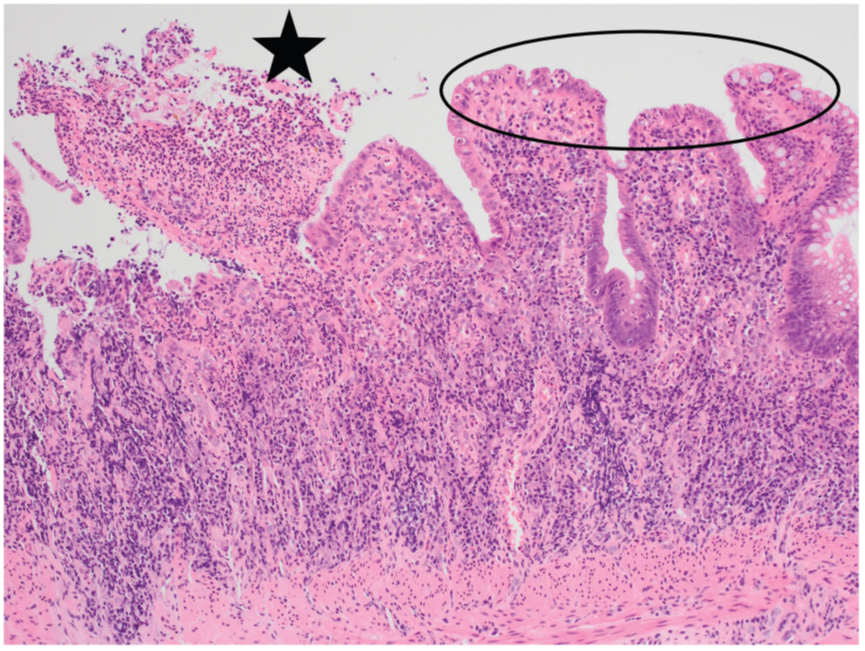

右侧腺体粘液分泌明显减少,可见凋亡和核分裂像,局部可见潘氏细胞化生